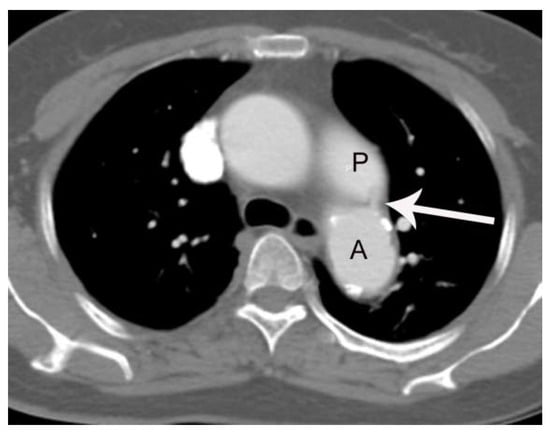

High Rate of False Negative Diagnosis of Silent Patent Ductus Arteriosus on the Chest CT with 3 mm Slice-Thickness, Suggesting the Need for Analysis with Thinner Slice Thickness